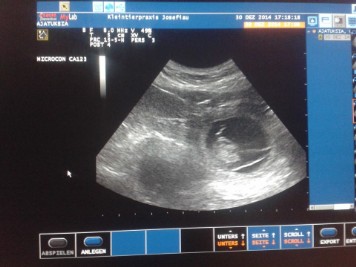

30.01.2014/ Day 25

The ultrasonic showed us at least 5 little puppies with beating heartbeats!